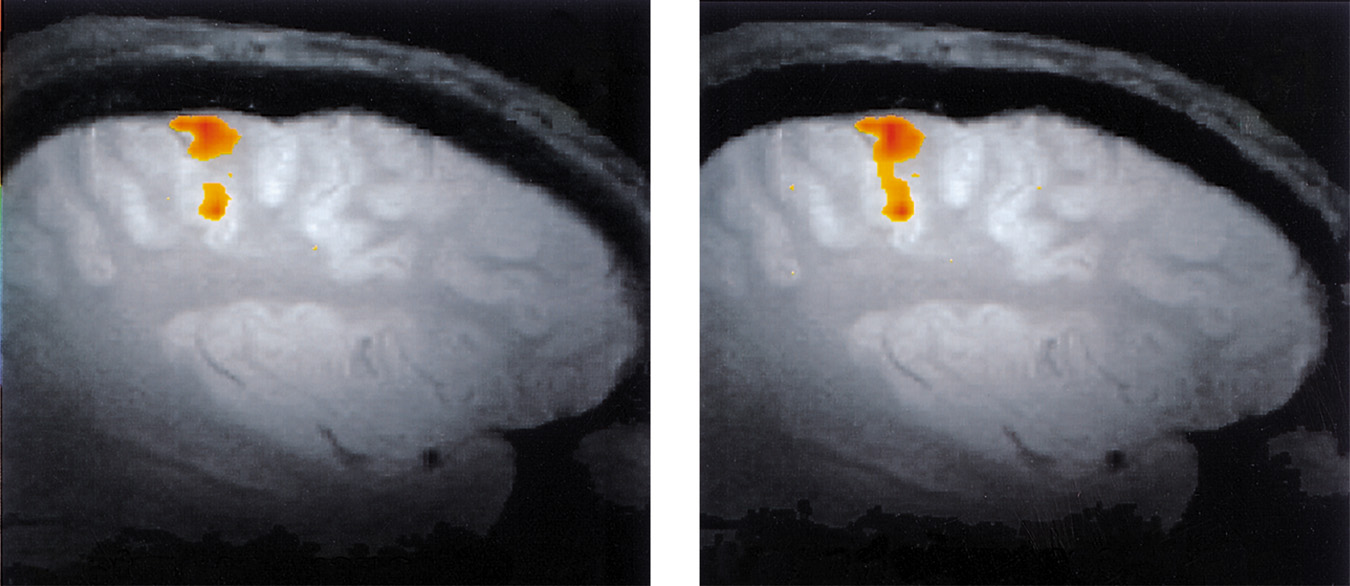

Visual Function

• Functional MRI scan shows the visual cortex activates as the subject looks at faces.

Auditory Function

• Functional MRI scan shows the auditory cortex is activated in patients who hallucinate (hear voices).